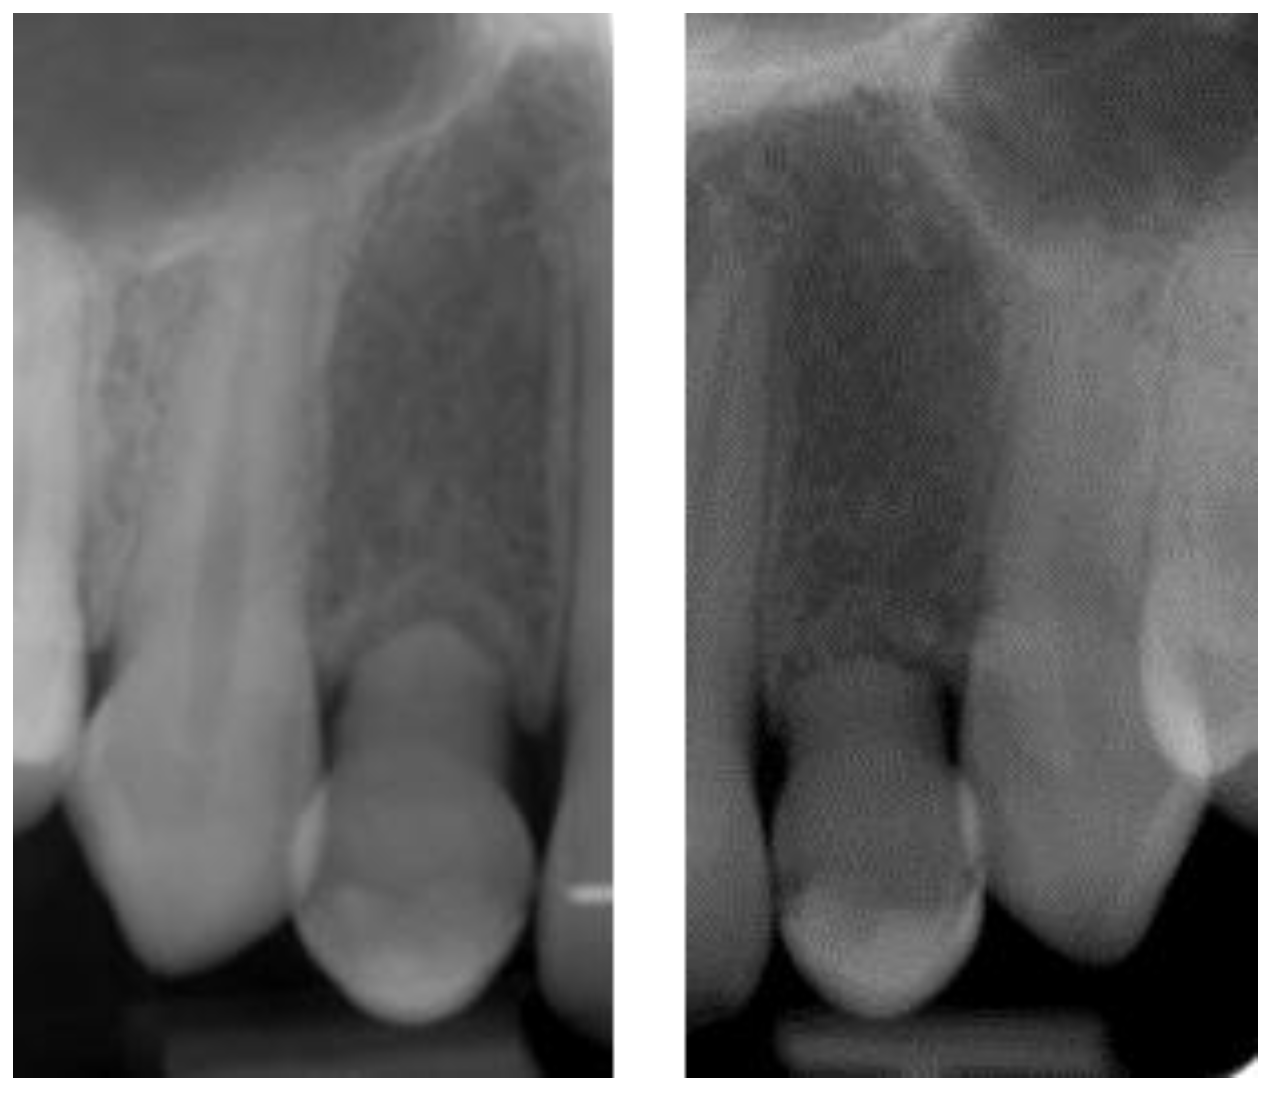

2.5. Individual Cases Description

- Case 1:

- Case 2:

- Case 3:

- Case 4:

- Case 5: